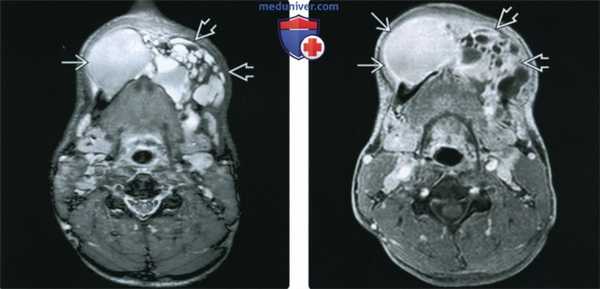

(Слева) На аксиальной МР-томограмме (STIR) визуализируется крупная амелобластома нижней челюсти, в составе которой находится массивный кистозный компонент (с правой стороны) с наличием уровней «жидкость-жидкость». Обратите внимание на многокамерный компонент с гиперинтенсивным сигналом на Т2ВИ (с левой стороны).

(Справа) При МРТ Т1ВИ FS сКУ в аксиальной проекции у это го же пациента с амелобластомой нижней челюсти определяется выраженное контрастное усиление стенок крупной однокамерной кисты, расположенной справа. Видны также множественные кисты меньшего размера с левой стороны.

(Слева) При MPT Т2ВИ с КУ в аксиальной проекции у пациента с амелобластомой верхней челюсти определяется солидный и кистозный (многокамерный) компонент. Обратите внимание на типичный интенсивный (Т2ВИ) сигнал в кистозном компоненте, а также экспансивное воздействие опухоли на заднюю стенку верхнечелюстной пазухи.

(Справа) На корональной (T1ВИ) томограмме с контрастным усилением и жироподавлением у этого же пациента определяется характерное контрастное усиление перегородок. Местно агрессивный характер амелобластомы также подтверждается ее распроаранением в полость носа и ячейки пазухи решетчатой кости.